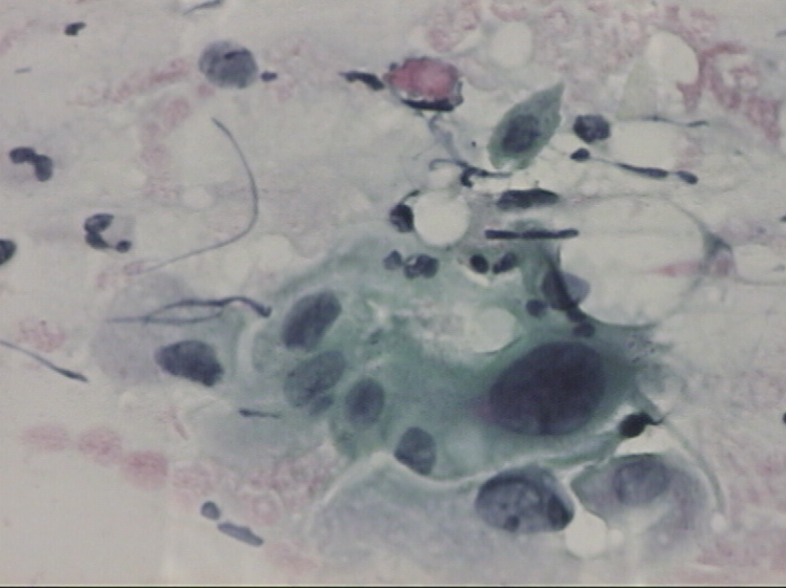

Here is an example of malignant cell findings. Malignant slides are ones that feature findings concerning for cancer or those that have dysplastic features.

Malignant characteristics include cells with irregular darkly-stained nuclei that are larger than normal nuclei.